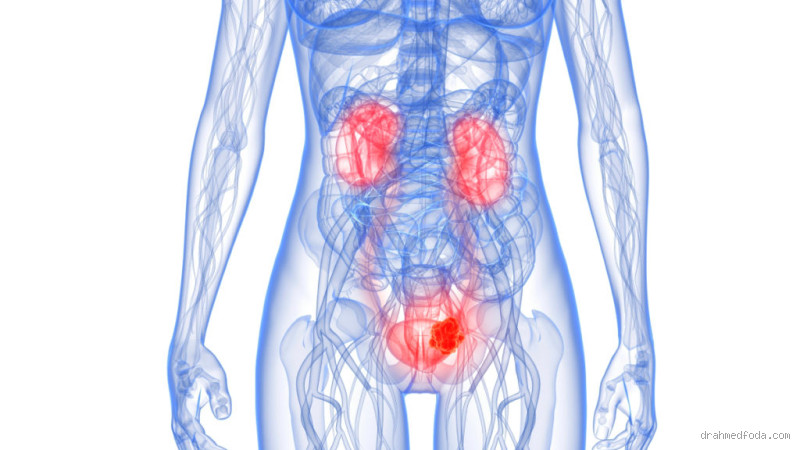

بداية، يجب أن نعرف أن التهاب المسالك البولية يحدث عندما تدخل البكتيريا إلى المسالك البولية، مما يؤدي إلى التهاب في المثانة أو الإحليل أو حتى الكلى. في معظم الأحيان، تحدث هذه العدوى بسبب البكتيريا المعروفة باسم الإيشيريشيا كولاي (E. coli)، والتي يمكن أن تنتقل من الأمعاء إلى المسالك البولية.

التهاب البروستاتا هو حالة شائعة يمكن أن تحدث نتيجة للعدوى في المسالك البولية، ويمكن أن يصاحبها ألم في الخصية. البروستاتا هي غدة صغيرة تحت المثانة، وإذا تأثرت بالعدوى، قد يشعر الرجل بألم في الخصية أو في منطقة الحوض بشكل عام.

حسنًا، الخصية هي جزء حساس من الجسم، وأي عدوى أو التهاب في المسالك البولية قد يمتد أحيانًا إلى منطقة الخصية. يحدث ذلك بشكل خاص إذا كانت العدوى شديدة أو مزمنة، مما يؤدي إلى شعور بالألم في أسفل البطن، وفي بعض الحالات، في الخصية أيضًا.

في الختام، نعم، التهاب المسالك البولية يمكن أن يسبب ألمًا في الخصية، خاصة إذا انتشرت العدوى إلى البروستاتا أو الأنسجة المحيطة بالخصية. إذا كنت تعاني من ألم في الخصية مع أعراض أخرى مثل الحرقان أثناء التبول أو التبول المتكرر، من المهم استشارة الطبيب بأسرع وقت ممكن. العلاج بالمضادات الحيوية يمكن أن يساعد في القضاء على العدوى وتخفيف الأعراض بشكل سريع.